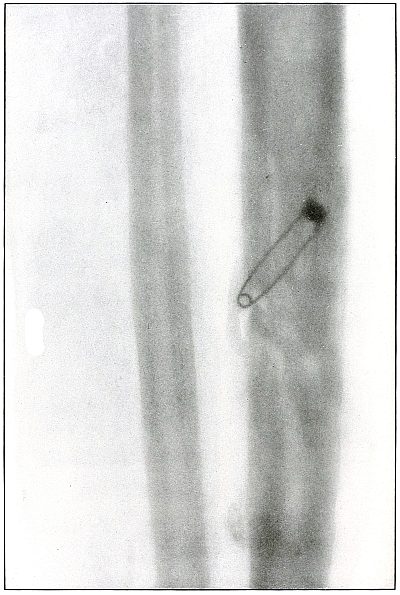

Plate 65.

_

[Pg 141]

Rifle—Plate 65.

LOWER EXTREMITY.

Gunshot Fracture of the Tibia.

The course of the bullet was transverse, from within outward, striking the bone near the outer border with the velocity of mid or long range, producing long fissures without separation of fragments.

The safety pin, of course, lies in the dressings and on the side away from the plate, as shown by its somewhat indefinite outline and increased length.

The wounds of entrance and exit are practically the same.

The treatment in such cases is that of a simple fracture, except for the management of an occasional infection, and the results are favorable. [Pg 142]